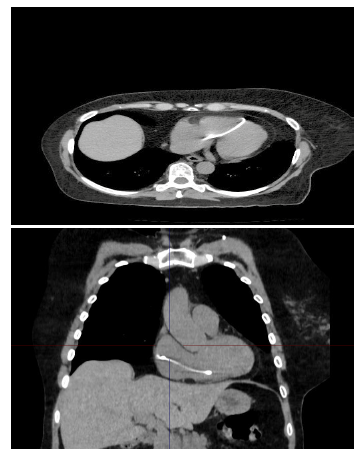

A comparison with a previous chest X-ray from 2024 confirmed a rupture of the subclavian port catheter (Figure 2).

Figure 2

Standard chest X-ray comparison. A) Reservoir catheter in the normal position along the internal jugular vein trajectory; B) The proximal end of the reservoir catheter is located in the right atrium and ventricle.

Source: SOLCA Hospital-Guayaquil.